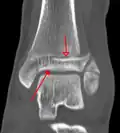

A triplane fracture of the ankle as seen on CT -

A triplane fracture of the ankle as seen on CT

CT

CT scans may be indicated when there is concern for a highly comminuted fracture or a fracture involving the joint surface.[10] This imaging may be used for surgical planning.